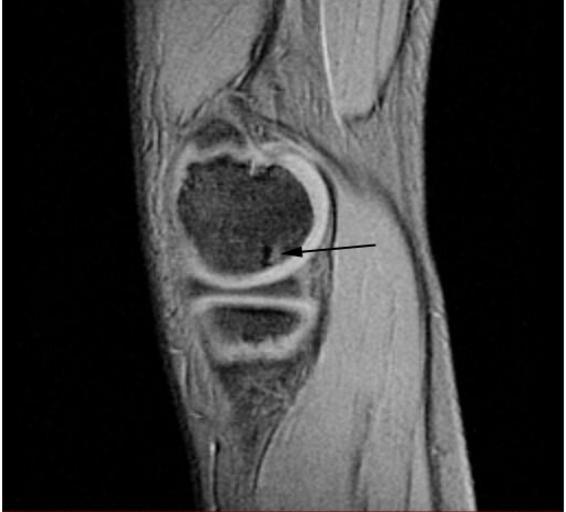

Keywords: OCD WalterReed MRI-Sagital-T2.jpeg en Sagittal and coronal T1 and T2 images demonstrate linear low T1 high T2 signal at the articular surfaces of the lateral aspects of the medial femoral condyles bilaterally corresponding to the radiographs confirming the presence of bilateral osteochondritis dissecans with diffuse increase in T2 signal at the medial femoral condyles indicating marrow edema From the case of a 9-year-old boy with bilateral knee pain Uniformed Services University Obtained from MedPix Database http //rad usuhs mil/medpix/medpix_image html imageid 14470 Pil Kang 2003-02-04 PD-USGov Magnetic resonance imaging of the knee MRI of osteochondritis dissecans |